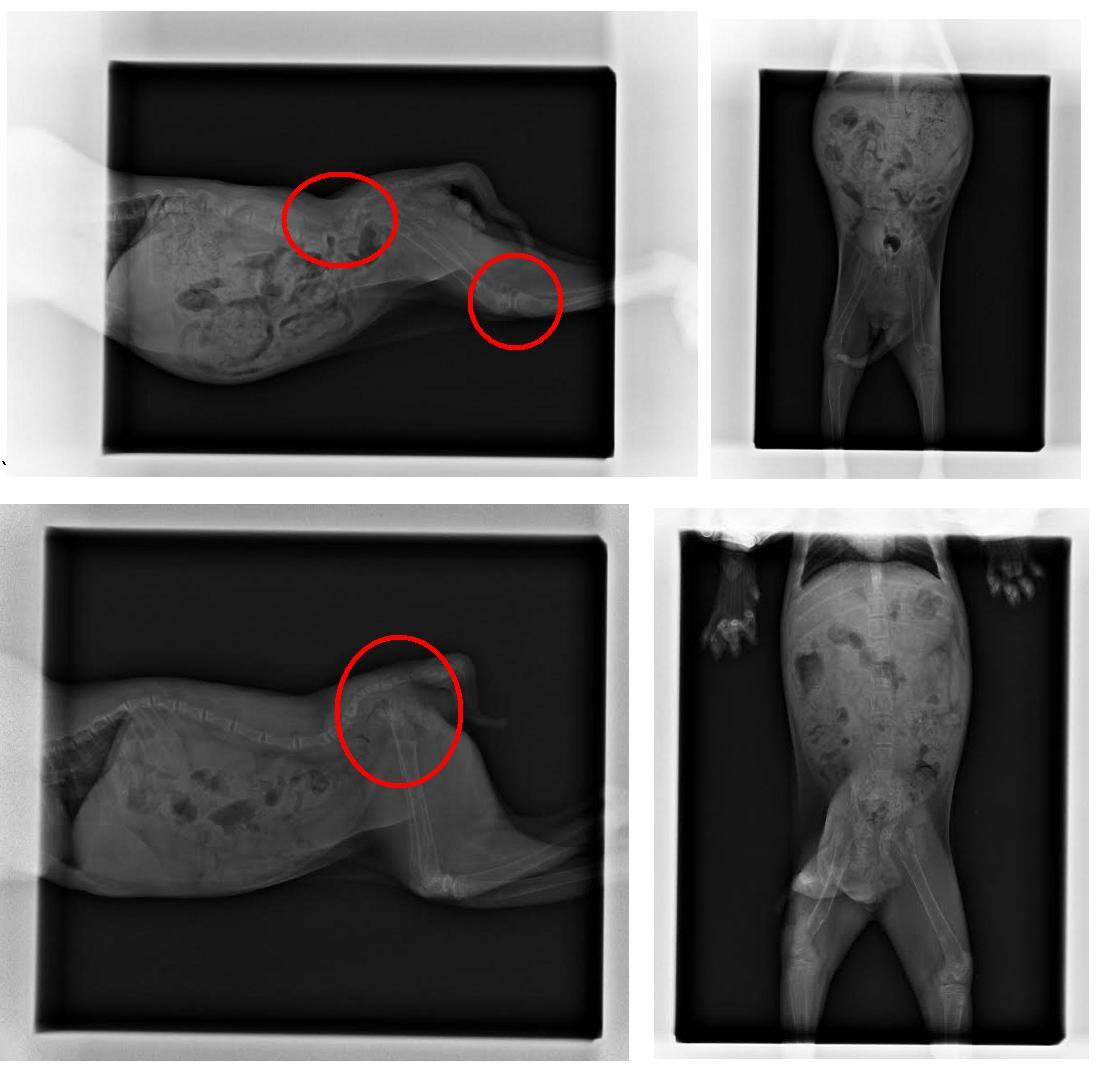

全虎斑貓咪-精神狀況差,無法自行行走,血檢報告顯示 鉀離子過低,X光顯示下脊椎.骨盆.股骨疑似病理性骨折

白底虎斑貓咪-精神狀況較佳,血檢報告顯示鉀離子過低,X光顯示下脊椎.骨盆.股骨疑似病理性骨折應該是病理性骨折...

3.x-RAY 400*2*2